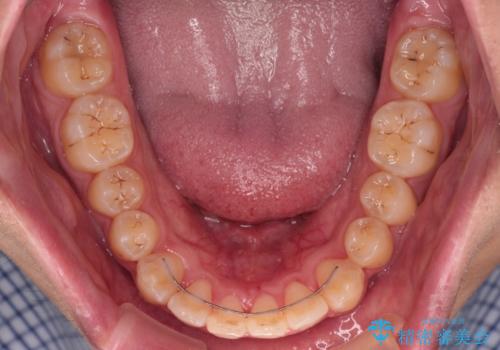

インビザラインで難儀する部分をワイヤー装置にて確実に改善しておくことで、インビザラインのみで行うよりも治療期間を短縮するとともに、より理想的な歯列に近づけて仕上げることができました。